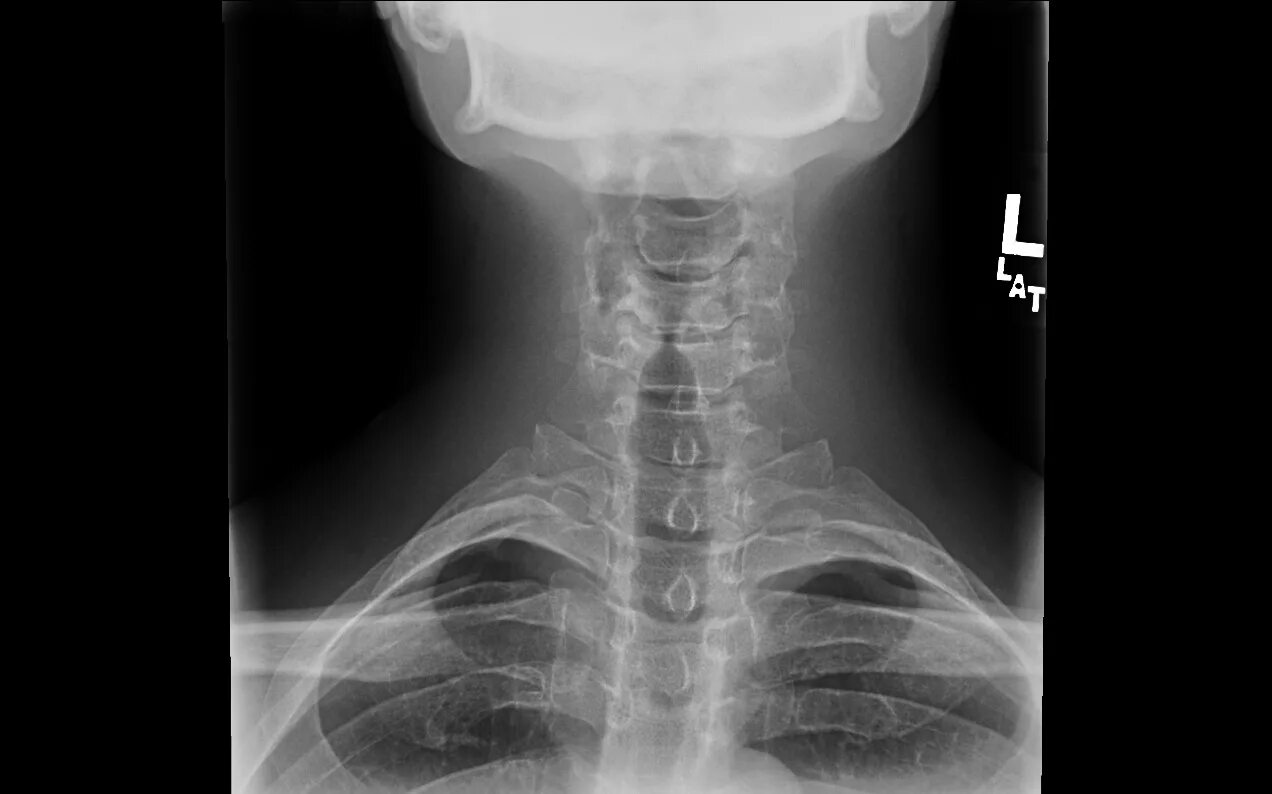

Снимок костей как называется